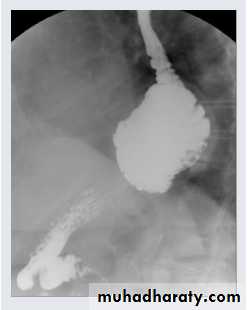

A barium swallow study demonstrates a large hiatal hernia with the majority of the stomach in the chest, not in the abdomen where it belongs.